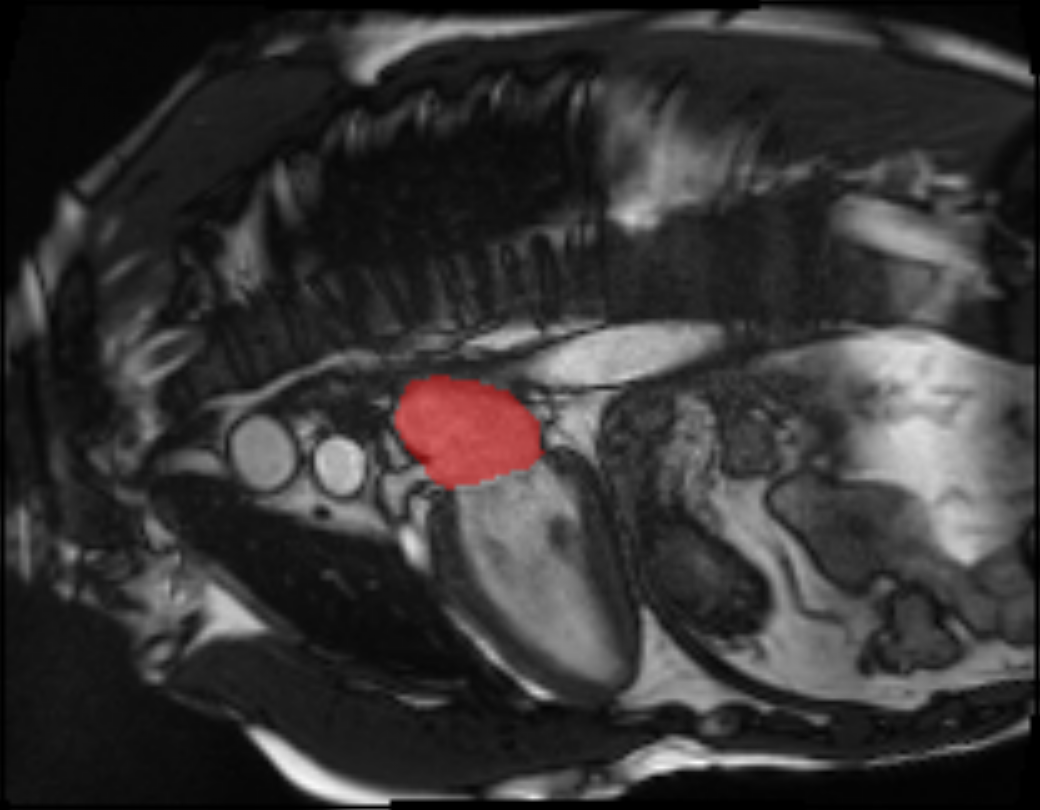

Our CUSSP method consists of five main steps, shown in Figure 4, with the first two steps representing data preprocessing, and the later three steps using network components trained for MR classification, as described in the next section. The pre-processing of the CMR imaging sequence is shown in Figure 8 in the Appendix. We used the segmentation model in 2.1 to locate the mitral valve and the orientation of the left ventricle. We then cropped a square patch with the mitral valve at its center positioned horizontally. After cropping, we applied histogram equalization to the patch with the pixel intensity range of the left atrium. The resulting patches are used by the downstream networks.

Refer to caption

Figure 8: Detailed overview of the pre-processing steps for CUSSP. Top: Example of the 4CH CMR images in the original contrast (left), the left atrium histogram equalized contrast (middle), and the cropped patch histogram equalized contrast (right), with blue contours outline the left atrium, and the red square boxes outline the patch to crop. Bottom: Example of the cropped mitral valve patch as outlined in the red square boxes in the top row.